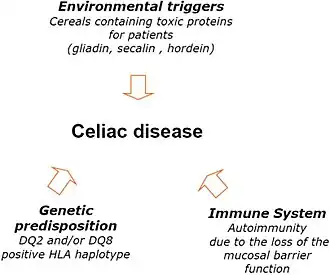

Coeliac disease (Commonwealth English) or celiac disease (American English) is a chronic autoimmune disease, mainly affecting the small intestine. It is caused by an abnormal immune system response to gluten, found in wheat and other grains such as barley and rye. Coeliac disease causes a wide range of symptoms and complications that can affect multiple organs outside of the gastrointestinal tract. The classic form of the disease can affect any age group, but is usually diagnosed in early childhood and causes symptoms of malabsorption such as weight loss, diarrhoea, and stunted growth. Non-classic coeliac disease is more commonly seen in adults, characterised by vague abdominal symptoms and complications in organs outside of the gastrointestinal tract, such as bone disease, anaemia, and other consequences of nutritional deficiencies. In people with a genetic predisposition to the condition, eating gluten causes inflammation in the small intestine, damaging its lining and leading to malabsorption. The development of coeliac disease is believed to be influenced by other environmental factors, such as infections.

Environmental factors such as infections, geographic latitude, birth weight, antibiotic use, intestinal microbiota, socioeconomic status, hygiene, breastfeeding, and the timing of introduction of gluten into an infant's diet are theorised to contribute to the development of coeliac disease in genetically predisposed individuals.[7][19][9] The consumption of gluten and timing of introduction in a baby's life does not appear to increase the risk of coeliac disease, however in those who are genetically predisposed to coeliac disease, large amounts of gluten early in life, may increase the risk of developing coeliac disease.[28][29]

Coeliac disease appears to be multifactorial, both in that more than one genetic factor can cause the disease and in that more than one factor is necessary for the disease to manifest in a person.[30]

Almost all people with coeliac disease have either the HLA-DQ2 variant (allele), or less commonly, the HLA-DQ8 allele.[8] However, about 40% of people without coeliac disease have also inherited either of these alleles.[31] This suggests that additional factors are needed for coeliac disease to develop; that is, the predisposing HLA risk allele is necessary but not sufficient to develop coeliac disease. Furthermore, a small percentage of those who do develop coeliac disease do not have typical HLA-DQ2 or HLA-DQ8 alleles.[8][32]